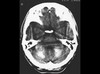

男性,62岁,四肢抽搐伴意识丧失反复发作